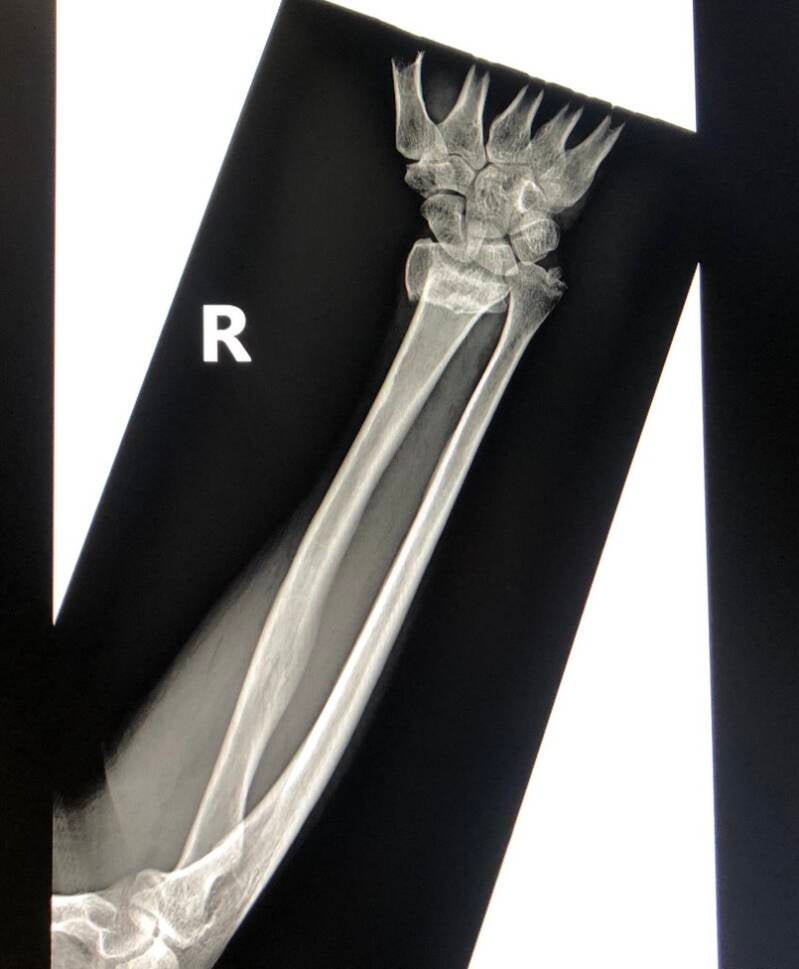

Everything goes like clockwork. Patricia drifts off to sleep. Ketamine and inhalational gases on board. Keith holds Patricia’s hand firmly. James applies an equal and opposite tractional force from Patricia’s elbow. The wrist reduces beautifully. The dinner fork again matches the set. Normal shape appears. An x-ray from Elvis confirms perfect positioning. James’ team applies plaster of Paris. The plaster sets quickly. After 5 minutes Elvis gives a second magic image. All set. Patricia is allowed to wake up. After 15 minutes of fame. Or should I say 15 minutes of drug induced torpor? Isoflurane gas now switched off. Patricia slowly rouses. Practically pain free and all set to safari again.

Before and after pictures. Working with Xray vision